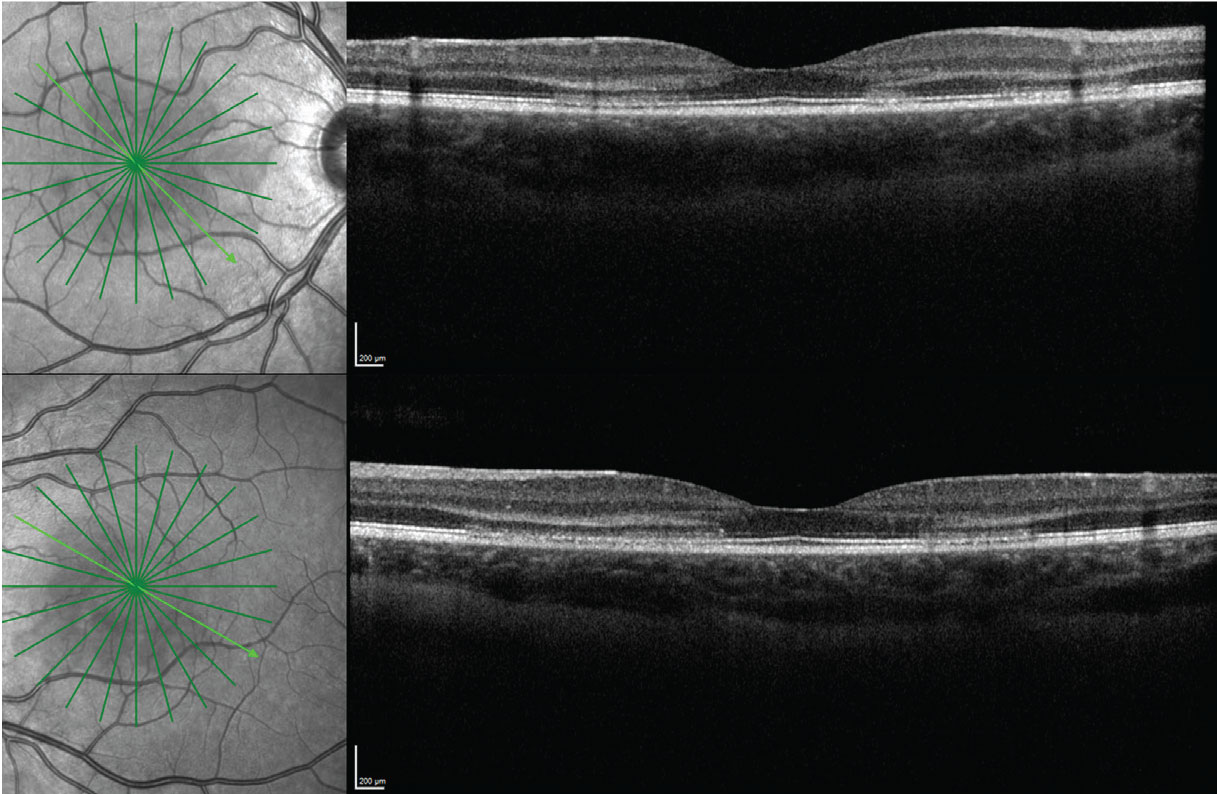

Funduscopic examination of both eyes demonstrated clear vitreous and normal optic discs (Figure 1). Subtle wedge-shaped gray lesions were noted in the macula of both eyes. The vessels and periphery were normal.

Optical coherence tomography of both eyes demonstrated multiple areas of outer retinal hyperreflectivity spanning the Henle fiber layer through the interdigitation zone and sparing the retinal pigment epithelium in both eyes (Figure 2).

Figure 1. Ultra-widefield fundus images of both eyes demonstrate subtle wedge-shaped gray lesions in the macula of both eyes. |

Figure 2. OCT of both eyes demonstrated multiple areas of outer retinal hyperreflectivity spanning the Henle fiber layer through the interdigitation zone and sparing the retinal pigment epithelium, in both eyes. |

This patient demonstrated striking hyperreflective changes involving multiple areas of the HFL in both eyes (Figure 2). The HFL comprises photoreceptor axons and Müller cell outer processes, and is oriented radially because the inner retinal elements migrate peripherally while the outer retinal elements migrate centrally during retinal development. This provides a less obstructed path for light and concentrates cones centrally.3 The radial pattern is why, for example, neuroretinitis classically demonstrates a macular star.